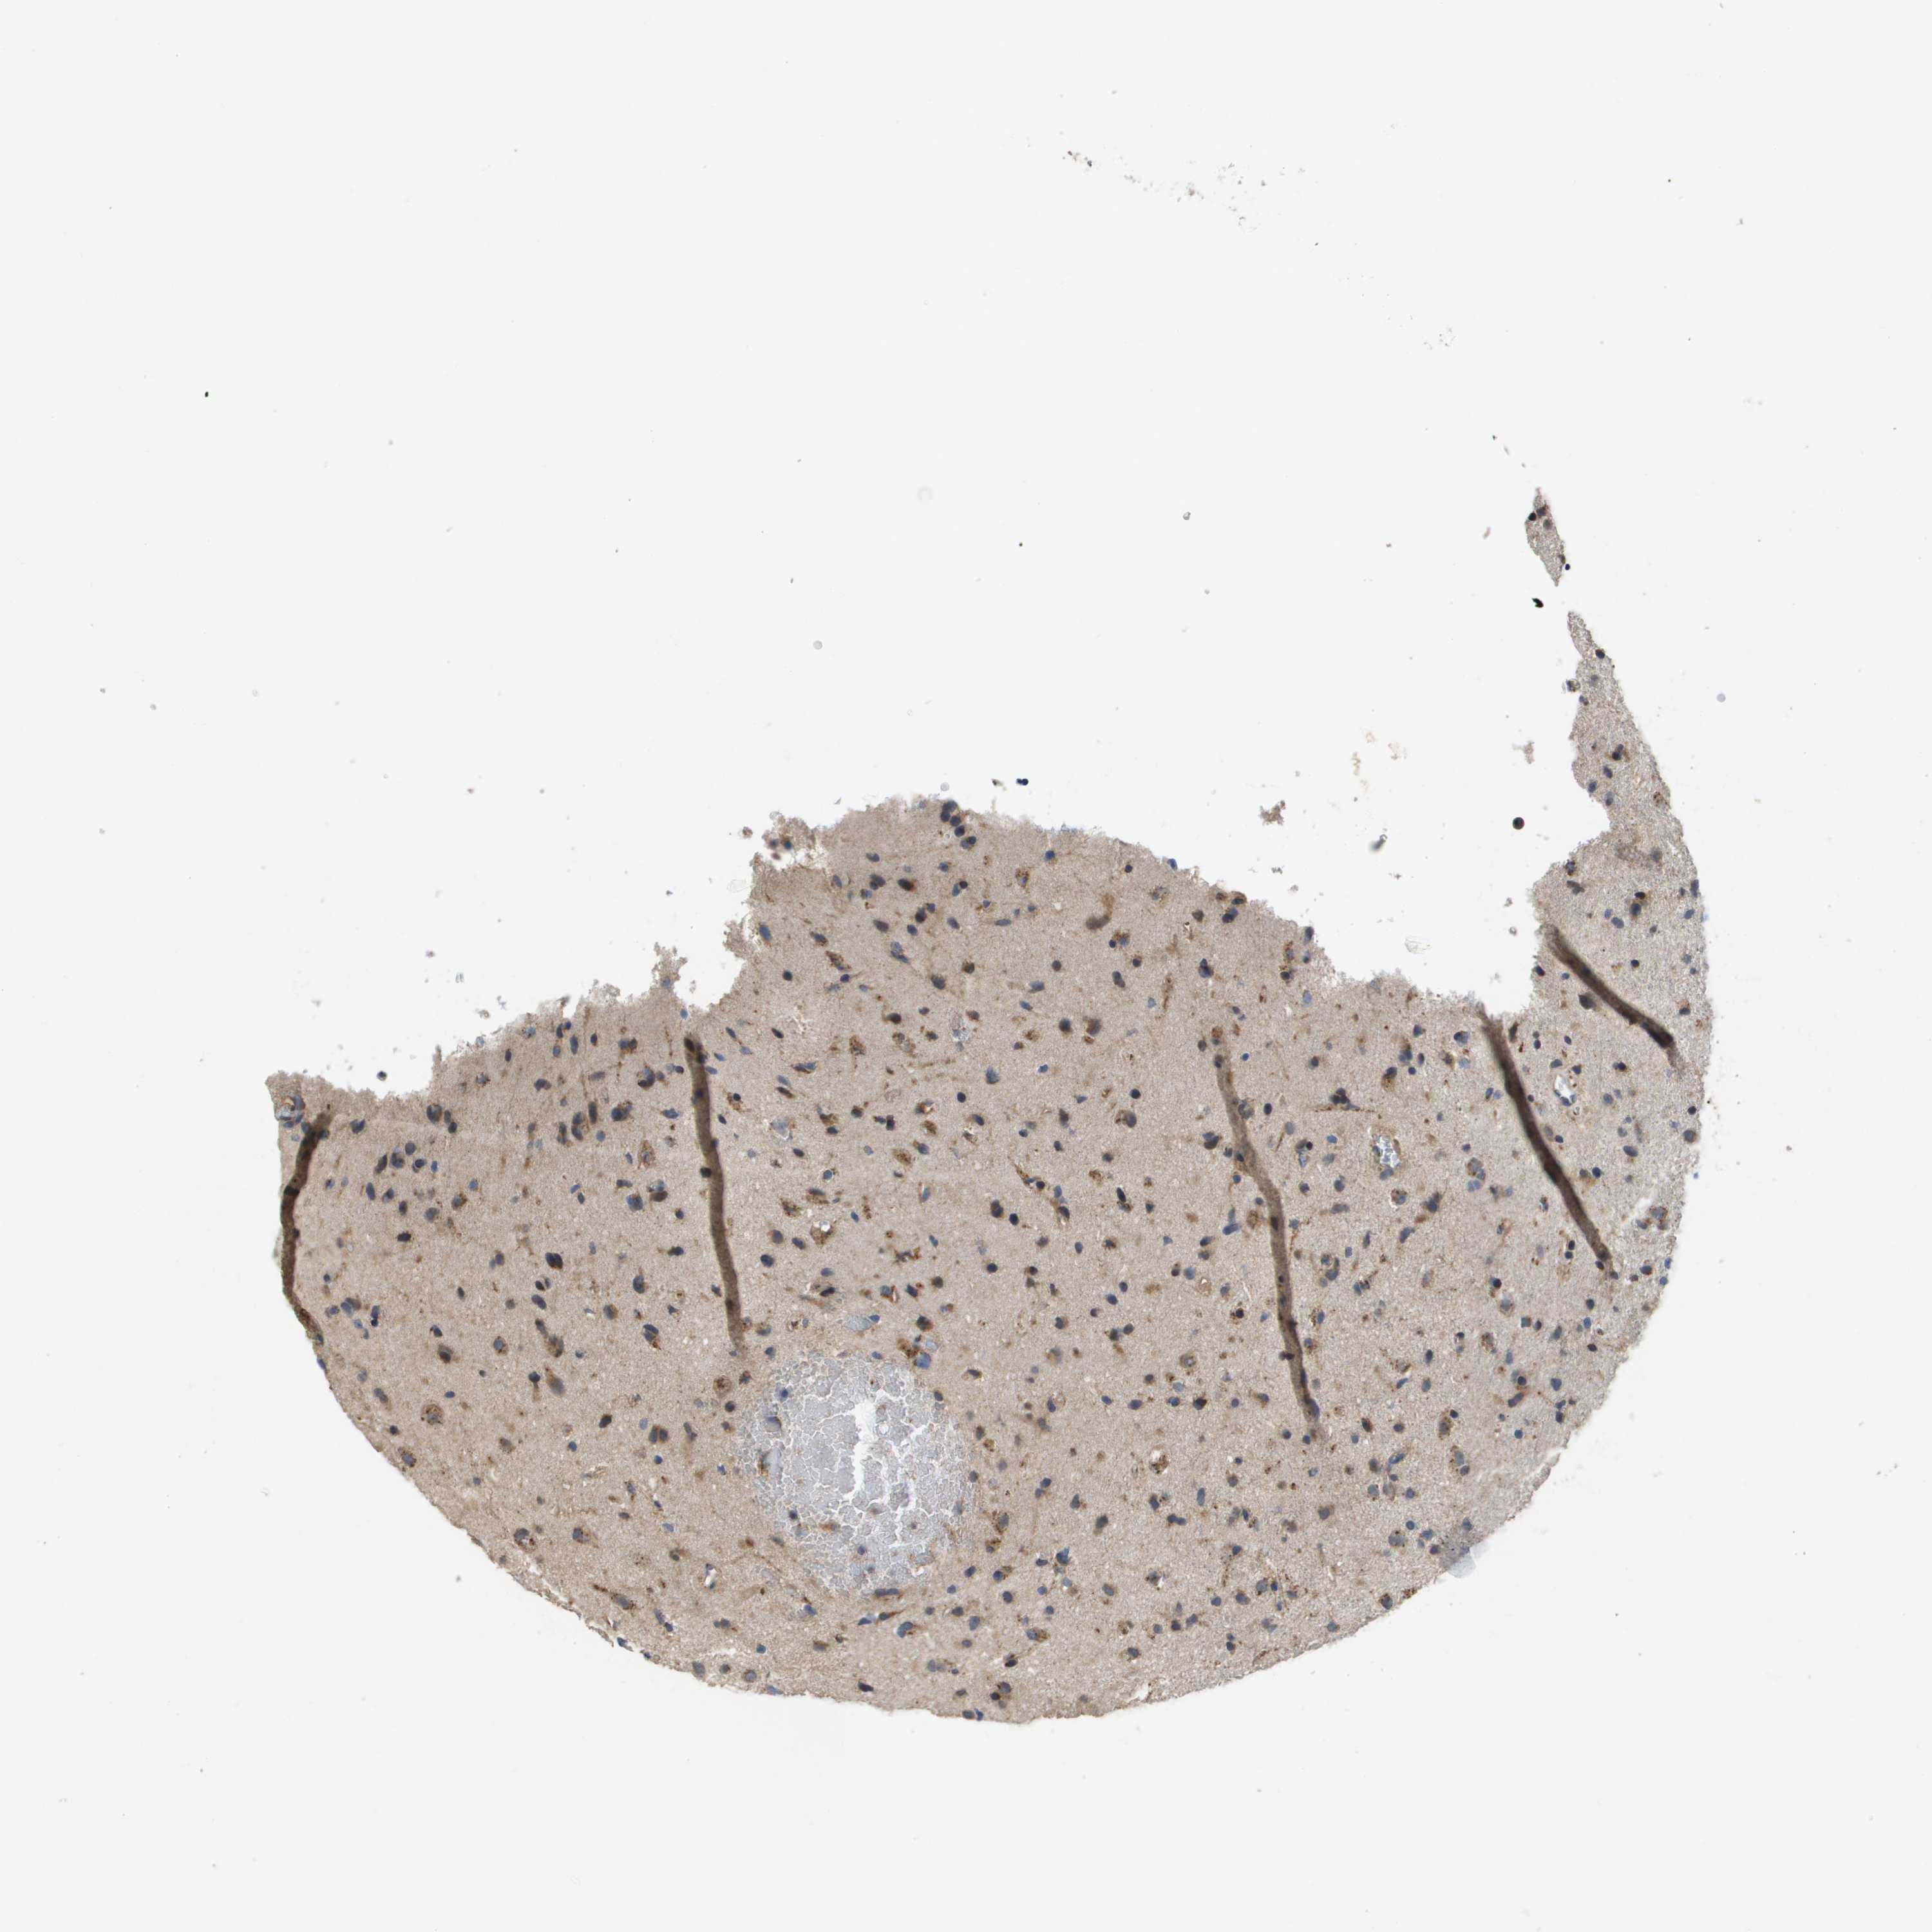

GLIOMA - Protein expressioni

A mouse-over function shows sample information and annotation data. Click on an image to view it in a full screen mode. Samples can be filtered based on level of antibody staining by selecting one or several of the following categories: high, medium, low and not detected. The assay and annotation is described here.

Note that samples used for immunohistochemistry by the Human Protein Atlas do not correspond to samples in the TCGA dataset.

Antibody stainingi

Antibody staining in the annotated cell types in the current human tissue is reported as not detected, low, medium, or high, based on conventional immunohistochemistry profiling in selected tissues. This score is based on the combination of the staining intensity and fraction of stained cells.

Each image is clickable and will lead to virtual microscopy that enables deeper exploration of all samples and also displays staining intensity scores, fraction scores and subcellular localization as well as patient and tissue information for each sample.

Antibody HPA006277

Antibody HPA006507

Antibody CAB017027

Staining

High

Medium

Low

Not detected

Intensity

Strong

Moderate

Weak

Negative

Quantity

>75%

75%-25%

<25%

None

Location

Nuclear

Cytoplasmic/membranous

Cytoplasmic/membranous,nuclear

Glioma, malignant, Low grade

Glioma, malignant, High grade